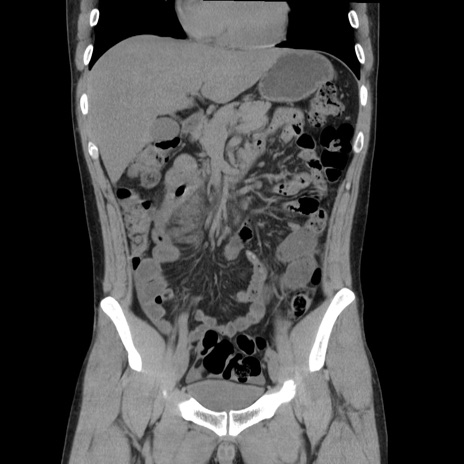

横断像

【症例】20歳代 男性

【主訴】心窩部痛

【現病歴】今朝より上腹部痛あり。一旦軽快していたが再度出現したため救急要請。昨日夕に白身の魚を含む刺身を食べた。

【身体所見】BP 136/89mmHg、HR 74/min、BT 37.0℃、腹部:膨満、軟、心窩部に圧痛あり。反跳痛なし、筋性防御なし、腸雑音やや亢進あり。

【データ】WBC 17700、CRP 0.48